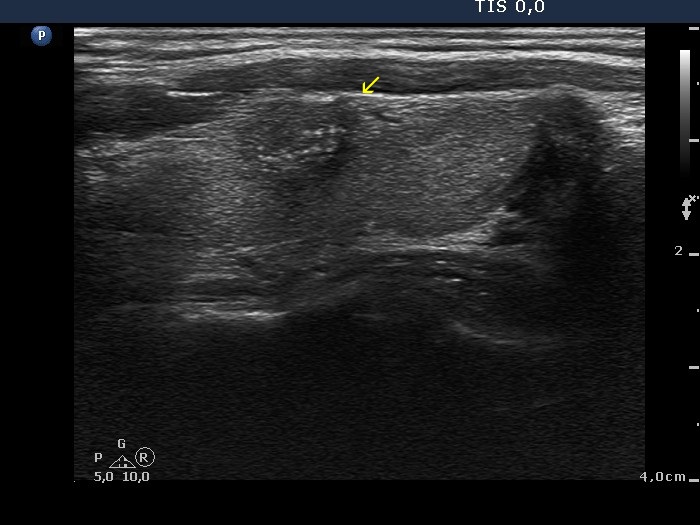

Longitudinal scan |

The lesion has partly blurred and partly spiculated margins. Although this presentation corresponds to thyroiditis, the fact that there are one or two relatively large lesions in the lobe should raise the possibility of nodular origin, namely papillary carcinoma. (Three types of indistinct borders are presented in these images. Green arrows point to that part of the nodule which echogenicity is identical to the extrathyroidal strap muscle. The tumor has partly blurred (red arrows) and partly spiculated (yellow arrows) margins. The extent of blurred part of the border exceeds 50%.)